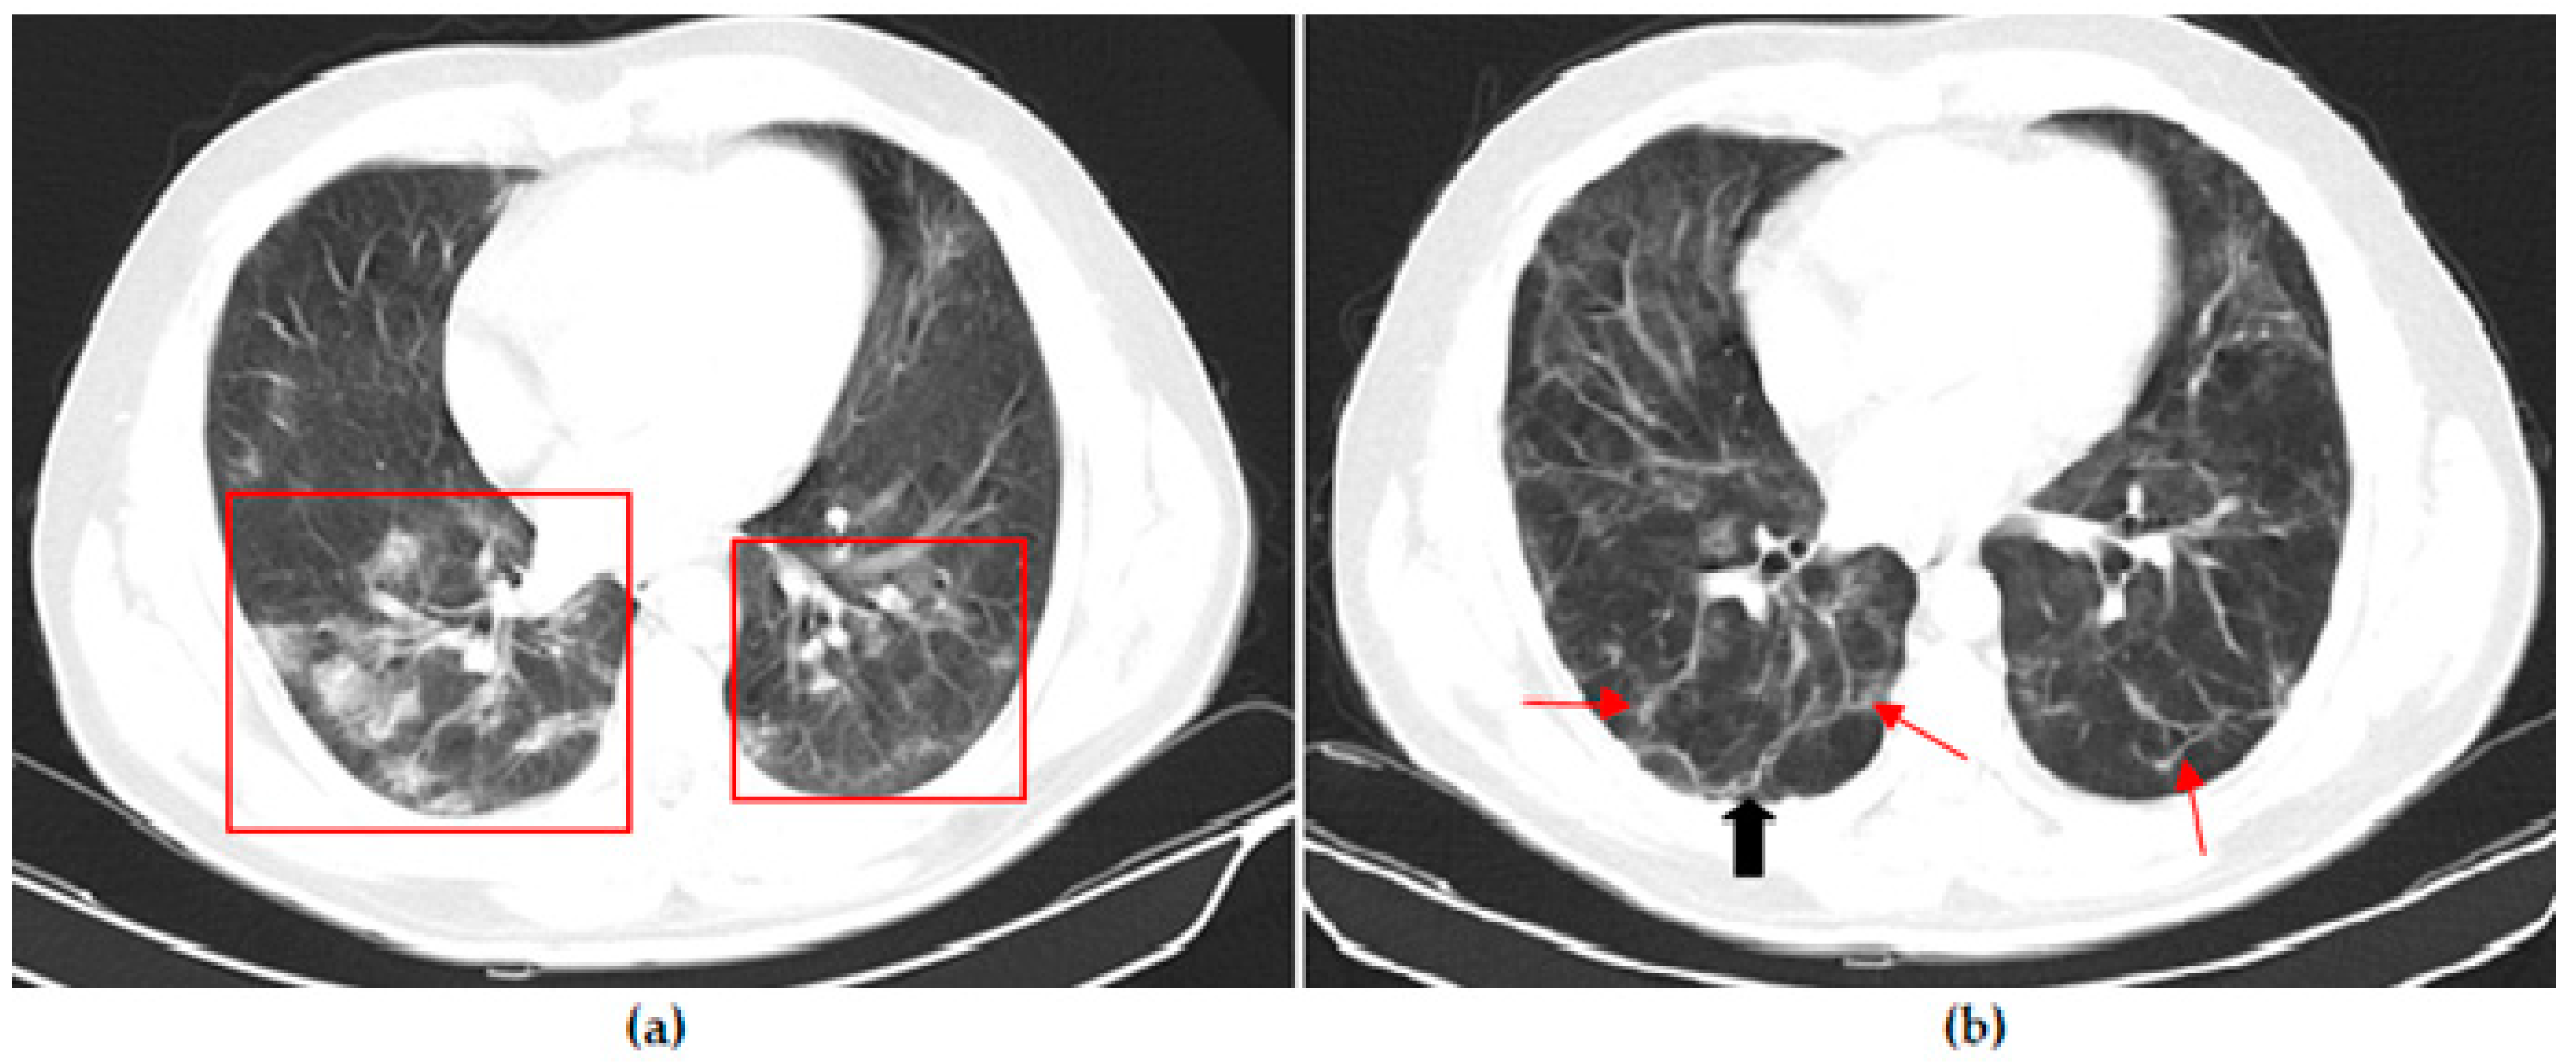

Thoracic CT images of a 43-year-old patient vaccinated with three doses of Biontech are shown in Figure 4.

Thoracic CT images of a 54-year-old patient vaccinated with two doses of Sinovac are shown in Figure 5.

Figure 4. A 53-year-old female COVID-19 patient vaccinated with three doses of Biontech presenting with fever for 3 days. (a) The axial thorax CT image shows a patchy ground glass opacities appearance (red frame) in the left upper lobe at presentation. (b) The 1st month follow-up axial thorax CT image shows the GGO appearance regressed, and no pathological findings were found.

Figure 5. A 54-year-old female COVID-19 patient vaccinated with two doses of Sinovac presenting with fever for 7 days. (a) The axial thorax CT image shows a patchy ground glass opacity (GGO) appearance in the bilateral upper lobes and the superior segment of both lower lobes (red frames) at presentation. (b) The 1st month and (c) 6th month follow-up axial thorax CT images show the GGO appearance of the bilateral lower lobes is lesser than previous CT scan. Multiple fibrotic parenchymal bands (red arrows) were found.